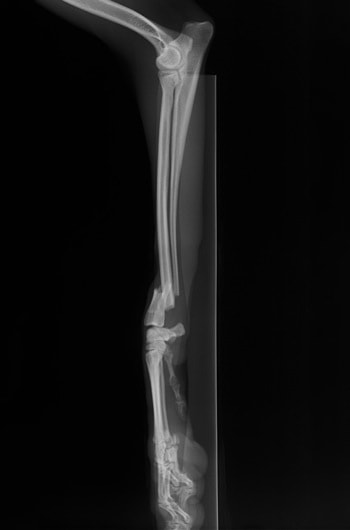

橈尺骨骨折 : 症例1 | 症例2 | 症例3 | 症例4 | 症例5 | 症例6 | 症例7

: 症例8 | 症例9 | 症例10 | 症例11 | 症例12 | 症例13 | 症例14

: 症例15 | 症例16 | 症例17 | 症例18 | 症例19 | 症例20 | 症例21